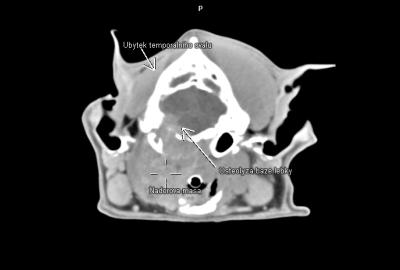

- nádory kostí lebky a čelistí,

V regionu hrtanu jednoznačně vedou nádory štítné žlázy(thyreoidey). Často se jedná o zhoubné varianty (karcinomy) s lokální invazivitou do struktur hrtanu a jazylky, s tendencí k tvorbě metastáz-mediastinum, plíce. Patří ale zároveň k nádorům poměrně často operovatelným. CT pak hraje v takovýchto případech zásadní diagnostickou roli.